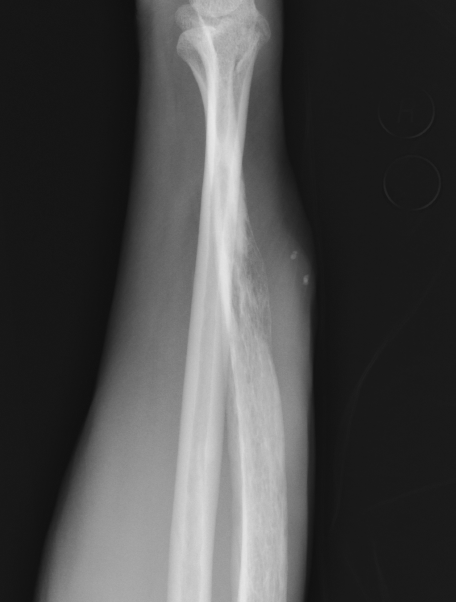

▌地图样破坏

地图样破坏是指肿瘤组织在一个局部呈团块状生长造成界限清楚的骨质破坏(图 1、图 2、图 3、图 4)。病灶可位于骨的中心或一侧部位,呈圆形、卵圆形密度减低区,与正常骨质分界清晰,边缘可有或无硬化带围绕,骨的形态无变化,病灶内可完全透亮或可见粗细不均、大小不等的残留骨嵴,内缘可光滑或呈分叶状压迹。地图样破坏见于大多数良性肿瘤和肿瘤样病变如单纯性骨囊肿、骨纤维结构不良、血管瘤等、也可见于部分恶性骨肿瘤如骨转移瘤、骨髓瘤等。

图 1.地图样破坏:单纯性骨囊肿